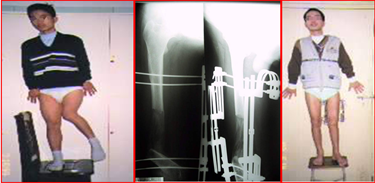

病例3:患者,男,16岁,股骨外髁不发育导致K型腿并短缩11公分。行外固定支架截骨矫形,延长11cm,骨痂生长良好。